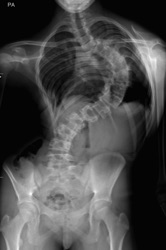

RADIOGRAPHIES DE LA SCOLIOSE

Les radiographies permettent de confirmer le diagnostic et de suivre l'évolution de la scoliose.

L'angle de Cobb mesuré entre les vertèbres les plus penchées de chaque courbure permet d'évaluer la sévérité de la scoliose et d'en suivre l'évolution.

Radiographies de la Scoliose - Angle de Cobb

Exemples de Scolioses Opérées - Arthrodèse Vertébrale